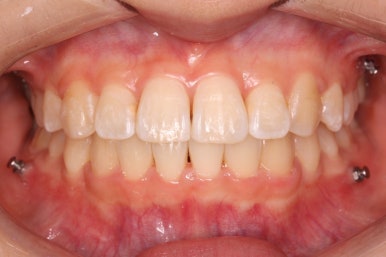

몇 달간의 마무리과정을 거치고 드디어 장치를 제거하였습니다.

위아래 앞니는 다시 틀어지지 말라고 유지철사를 붙였습니다.

위에는 탈착이 가능한 유지장치도 사용합니다. 2중으로 안전장치를 하는 것이죠.

치아는 매우 가지런해졌고, 과개교합도 개선이 되었으며 뻐드러진 앞니 각도도 정상적으로 회복이 되었습니다.

전후사진을 비교해 보겠습니다.

나란히 놓고 보면 차이가 극명하게 납니다.

치아가 가지런해졌습니다.

뻐드러진 앞니가 정상적인 각도로 회복되었습니다.

전반적인 치아들의 위치가 뒤로 이동하였습니다.